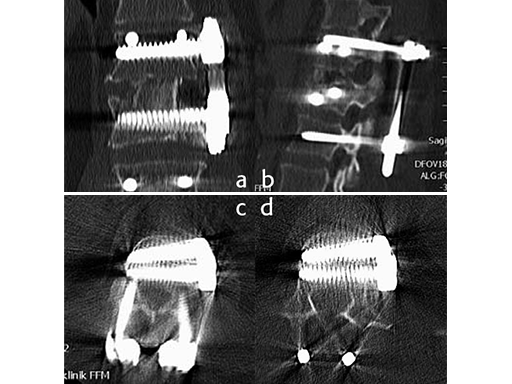

As a result of the ruptured disc and the fractured superior endplate, a hemivertebrectomy was performed and reconstruction was performed using an autologous iliac crest bone graft. To keep the graft in place and to allow for early posterior implant removal, an ArcoFix plate was used, allowing for slight compression as well as final sagittal reconstruction.

The hemivertebrectomy and the placement of the bone graft and ArcoFix plate were performed applying thorascopically assisted surgical technique.

Follow up CT Scans (AP, lateral and coronal) after the second surgery.